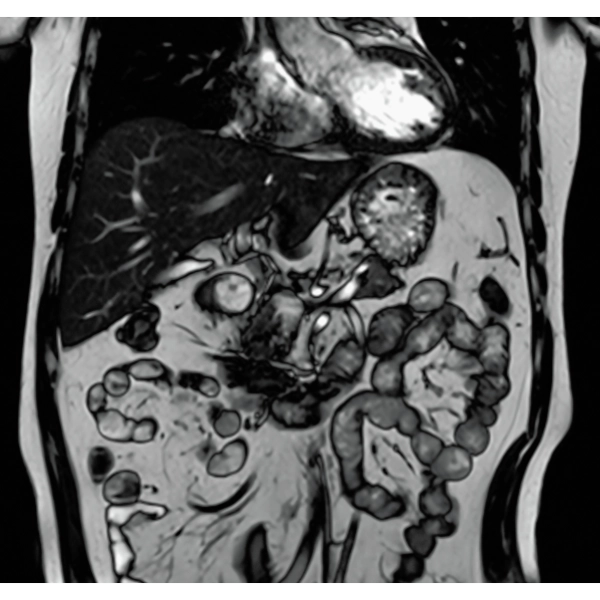

When motion artifacts occurs in the image due to coughing, sneezing, or involuntary movements, either or both the visual information acquired by monitoring cameras, Synergy Vision, and the intrabody information acquired by the navigator pulse can be used to provide an image with reduced artifacts. This reduces the re-imaging rate.

Body movements that affect image quality are detected from monitoring cameras based on thresholds derived for each body part.

Movements within the body are detected by navigator pulses. Body movements that significantly affect image quality are detected based on the error between pulses.